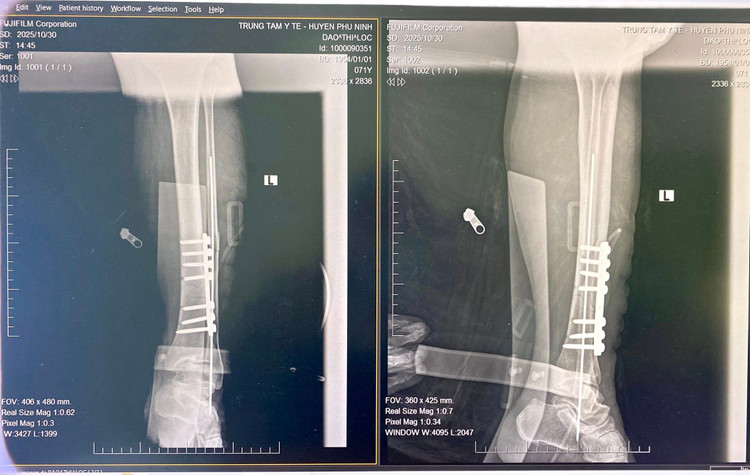

Sau 45 phút khẩn trương, ê-kíp phẫu thuật đã tiến hành ca mổ trong điều kiện vô khuẩn tuyệt đối. Với tay nghề vững vàng, thao tác chính xác và sự phối hợp nhịp nhàng, ca phẫu thuật diễn ra an toàn, thuận lợi. Hậu phẫu, người bệnh tỉnh táo, vết mổ khô, chi được cố định tốt, cảm giác và vận động dần hồi phục.

gay-xuong.jpg

Ê -kíp phẫu thuật cho bệnh nhân - Ảnh BVCC

gay-xuong-3.jpg

Nẹp vít xương gãy sau phẫu thuật - Ảnh BVCC